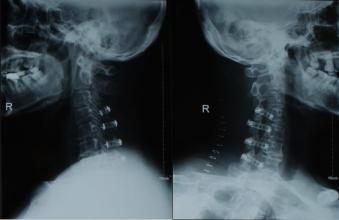

8.固定

為防止植骨壓縮,可用頸椎前路鋼板固定,現(xiàn)多為鈦質(zhì),術(shù)后仍可行MRI檢查。

術(shù)后處理:

爆裂骨折者術(shù)后繼續(xù)顱骨牽引3周,以穩(wěn)定頸椎,行鋼板固定者則不用牽引可用頸圍,引流條于48h拔除。一般3個(gè)月頸椎可融合,由于本手術(shù)對(duì)硬膜前的干擾,術(shù)后可用地塞米松及脫水藥3~5d。